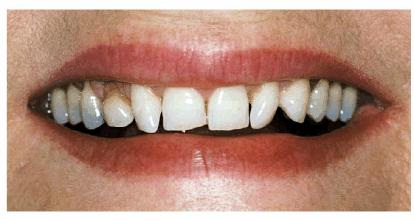

Esthetic Contouring and Porcelain Laminates to Eliminate Crowding

PROBLEM: This 58-year-old housewife was concerned about her eroded,

crowded, and stained front teeth (Figures 24-5A, and 24-5B). Measurement with a dental dial

caliper helped to accurately determine available space for reproportioning tooth

size (Figure 24-5C). Although orthodontics was

mentioned as a first step to an ideal solution, the patient preferred to accept

a compromise treatment of porcelain laminates and cosmetic contouring. Although

crowding was less of a concern to the patient (Figures 24-5D, and 24-5E), she nevertheless decided to have

straighter-looking teeth through a compromise treatment of porcelain laminates

that would also esthetically correct the erosion and discoloration.

Figure 24-5A: This 58-year-old woman was dissatisfied with her crowded, eroded, and discolored teeth.

Figure 24-5B: Preoperative view.

TREATMENT: Figure 24-5D shows the areas that will be

esthetically contoured. Following contouring to reproportion spaces, Figure 24-5F demonstrates the gingival chamfer

margin being placed with a two-grit LVS diamond bur (Brasseler). The occlusal

view (Figure 24-5G) reveals just how much overlapping

existed. Figure 24-5H shows the teeth after esthetic

contouring and tooth preparation have occurred, as well as how defective

amalgam restorations were removed and glass ionomer bases were placed. Figure 24-5E shows finished laminates in place.

Note the newly proportioned, straighter, and lighter-looking teeth. The final

occlusal view also shows a new arch created by the laminates, building out

teeth #9 and #10 and the new posterior laminate onlays on the upper right side.

RESULT: Before and after smiles can be seen

by comparing Figures 24-5B, and 24-5I. Esthetic contouring has also

improved the alignment of the lower anteriors. Constructing the porcelain

laminates indirectly allows the laboratory to better proportion tooth size.

Figure 24-5I: Postoperative view of improved smile created by use of porcelain laminate veneers and esthetic contouring.